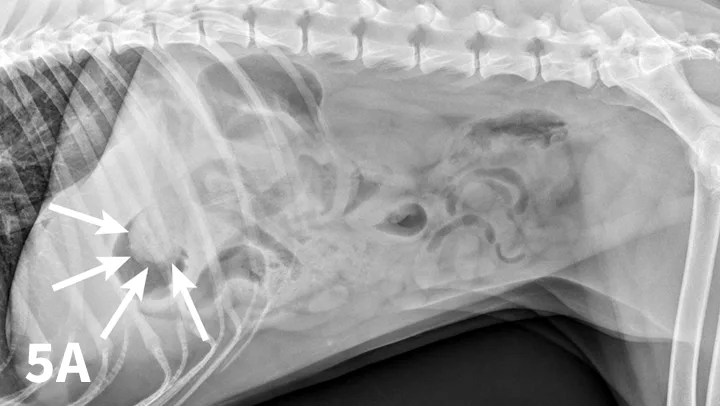

Radiographic features of small intestinal mechanical obstruction depend on its completeness, location, and duration.2 Whereas metallic FBs or those with mineral content are easily recognized within the GI lumen (Figure 1), nonmineralized, nonmetallic objects (eg, cloth) within the GI tract are more difficult to identify (Figure 2). Some may be recognized by their geometric shape. The most consistent sign of mechanical obstruction is variable dilation of intestinal loops proximal (orad) to the obstruction (described as a mixed population of small intestine; Figure 2). Determination of small intestinal diameter can be made by comparing it to the L5 vertebral body height in dogs.3 Values greater than 1.6 are suggestive of obstruction (Figure 2A). In cats, a ratio of the maximum small intestinal diameter to vertebral end plate height of L2 greater than 4 indicates a high likelihood of intestinal obstruction.4

Qualitative assessment of intestinal size by experienced clinicians may be as accurate in determining the presence of mechanical obstruction as calculation of ratios. Obstructed intestine usually contains fluid and gas; however, if the obstruction is orad, reflux into the stomach can occur and limited intestinal distension may be apparent. More distal (aborad) or more complete obstruction leads to greater dilation. Stacking of intestinal loops occurs with more severe dilation as segments become increasingly crowded in a relatively smaller space (Figure 2B).

FIGURE 2

Right lateral (A) and VD (B) abdominal radiographs of a Labrador retriever with an obstructive ileus. A FB (sock) is present within a dilated small intestinal loop in the right caudoventral abdomen (arrows). The dashed lines outline a fluid-filled loop measuring 2.7 cm and a gas-filled loop measuring 2.4 cm, compared to the height of L5 (Asolid line, 1.1 cm);  the resulting ratios of 2.4 and 2.2, respectively, are much greater than the upper limit of 1.6 for normal small intestine to L5 height ratio. Several stacked gas-filled loops of small intestine are present in the left midabdomen (B).